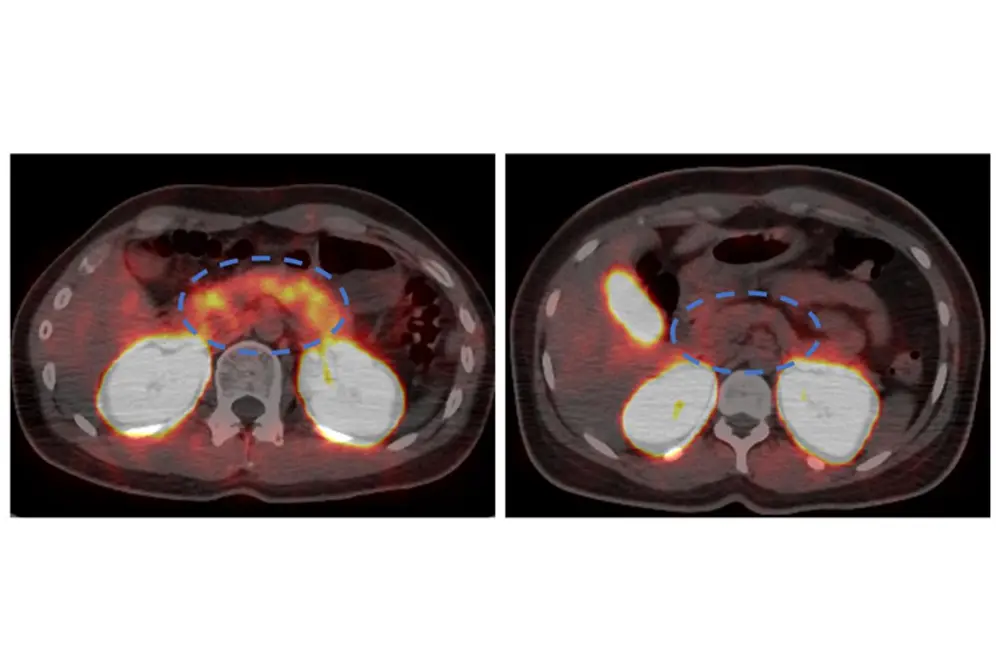

1型糖尿病患者と健常者の膵臓領域を比較したPET/CT画像

1型糖尿病患者(左)と健常者(右)のPET/CT画像。青い点線で囲まれた膵臓領域で、1型糖尿病患者ではシグナルの低下が確認される。(出典:京都大学)

• 1型糖尿病患者では健康な人より膵臓の画像シグナルが低く、β細胞量の減少が確認された。

解析の結果、1型糖尿病患者では健康な人と比べて膵臓の画像シグナルが低く、β細胞量が減少していることが示された。

特に、膵臓でほとんどインスリンを作れなくなっている患者では、健康な人との違いが明確に確認された。